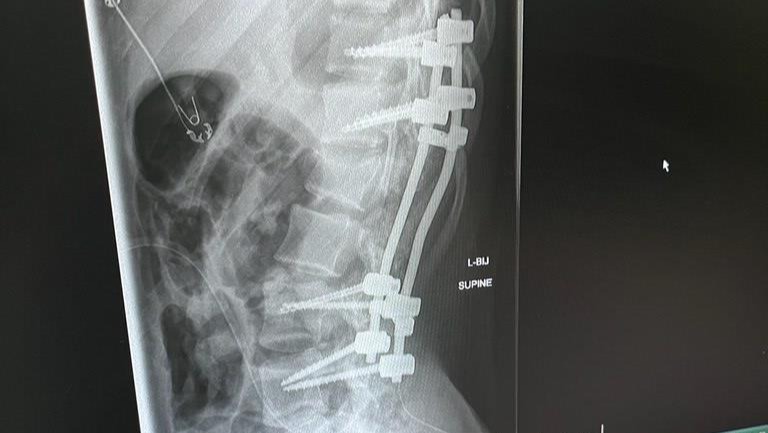

My name is Greg, and I am Abby's cousin. Recently Abby Camargo was in a tragic snowboarding accident while on school vacation where she landed on her back and has endured some severe trauma towards her spine. She burst her L1 disc in her back and has some nerve damage as well as a broken vertebrate.

Abby has undergone corrective surgery and is facing a lot of rehabilitation ahead of her. Doctors have put a nine and a half inch rod to help stabilize and fuse her spine. She is currently in the PICU for the foreseeable future, where she will then will be moved home to recover for an additional few months. We are all thankful that she had the top care and support that she needs at this time. The cost towards this procedure and rehabilitation is certainly astronomical towards Abby and her family. All donations are beyond helpful and will go towards paying Abby's medical expenses.